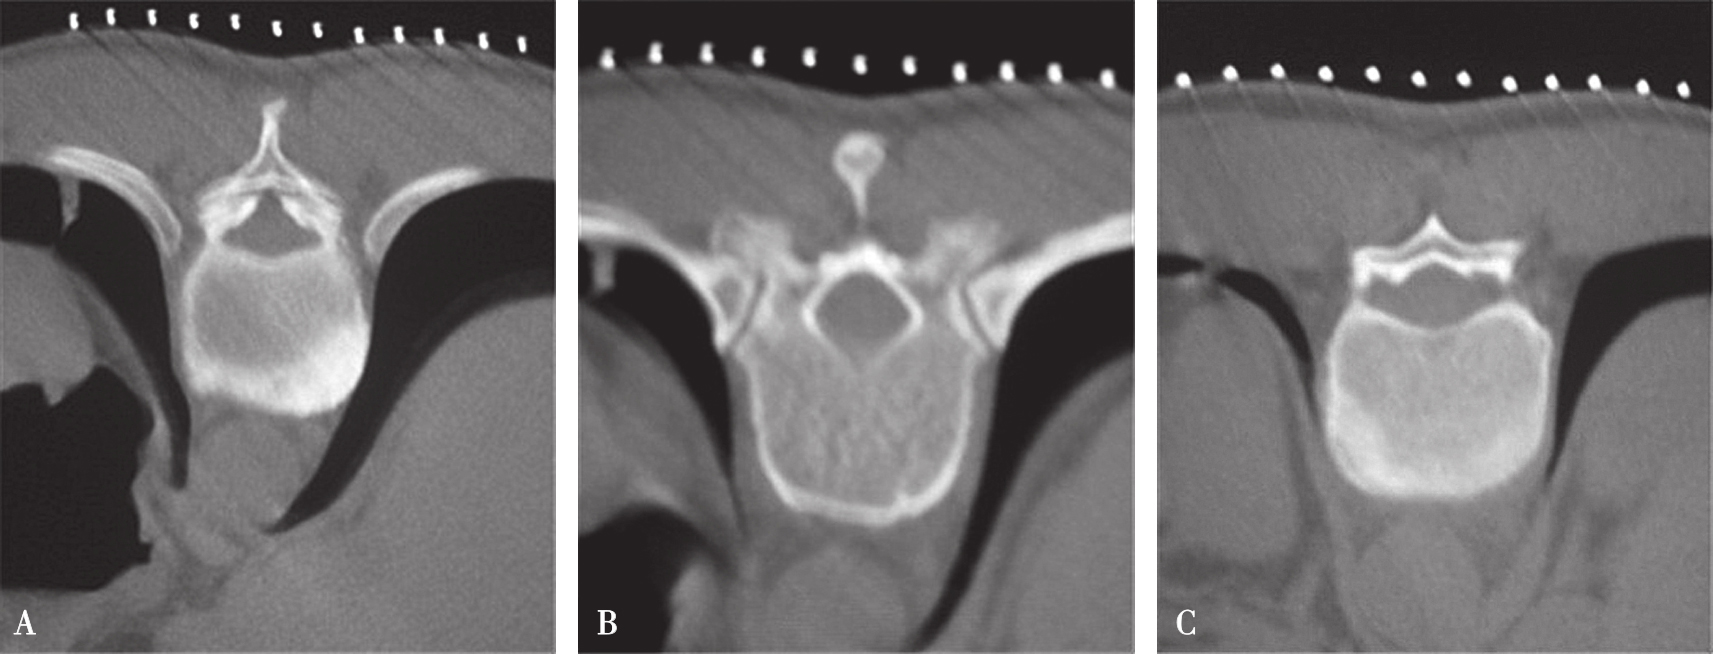

一般的CT机架可以调整角度(图3-3-8),调整机架角度进行扫描是寻找操作平面的关键举措,不同的穿刺途径和手术目的要求机架调整的角度也不同,如L 4/5 经椎间隙侧方入路时,如果手术平面无髂骨阻挡,则采用零度扫描(见图3-3-6A、图3-3-8B),否则为了避开髂骨阻挡,机架应向头侧倾斜(图3-3-6B、图3-3-8C);用于射频靶点消融或内镜髓核摘除的椎板间入路,如果扫描角度与椎间隙平行,将多有椎板阻挡(图3-3-9),其要点在于穿刺靶点为直接突出的椎间盘,而穿刺途径又必须避开椎板经过椎板间隙才能成功,因此要求调整到既能显示靶点又经过椎板间隙的角度,一般向足侧倾斜(图3-3-8A、图3-3-10);椎弓根入路则沿椎弓根轴线扫描(图3-3-11)。

图3-3-9 机架平行椎间隙扫描

A.沿椎间隙轴线扫描(红坐标线);B.横断位层面多有椎板阻挡

图3-3-10 适当角度扫描

A.经过椎板间隙的角度扫描(红坐标线);B.寻找出符合手术要求的操作平面